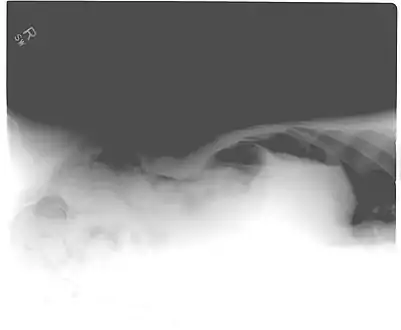

Another pneumoperitoneum on chest X-ray.

Another pneumoperitoneum on chest X-ray. Pneumoperitoneum seen on X-ray with the patient lying on his left side.